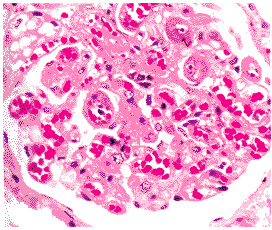

SLE有全身各系統臟器的損害同樣可直接損害胎盤,導致胎盤功能不全者可達30%(SLE活動型和穩定型胎盤功能不全分別為47.6%18%),腎型SLE伴高血壓孕婦因子宮胎盤血管痙攣致胎盤功能不全的發生率更明顯增高。已證實SLE抗體能損傷胎盤,使胎盤發育不良。這種免疫損傷引起小血管壁缺血、缺氧及纖維素樣壞死和急性動脈粥樣硬化,造成胎盤發育不良,絨毛面積減少物質交換功能受影響,胎兒獲得營養減少是導致SLE孕婦流產、胎死宮內、胎兒生長遲緩(IUGR)發生的重要原因。在妊娠晚期胎兒極易發生宮內窘迫。

症狀SLE患者多為緩慢起病,隨著所累及的器官系統不同,主訴及症狀亦有不同,根據Hahn(1998)的資料,臨床症狀及發生率如下:95%的患者有全身症狀包括發熱、疲倦乏力體重減輕和周身不適SLE患者約95%出現骨骼肌肉症狀,包括嚴重關節疼痛,表現為對稱性關節炎,半數有關節晨僵,肌肉疼痛、乏力,嚴重者肌肉萎縮。85%SLE患者有血液系統改變,包括貧血、溶血、白細胞減少、血小板減少血清中有狼瘡抗凝物。大約有80%的SLE患者出現皮膚損害,突出的特點是面部蝶形紅斑,分布於鼻及雙頰部,少數紅斑也見於其他部位,紅斑稍微水腫,日曬後加重。肢端可有小結節及雷諾現象皮膚彈力差。可以有脫髮,口腔潰瘍。60%的SLE患者有精神、神經症狀約50%患者有腎炎和精神、神經症狀,表現極不一致,輕者僅有心理障礙如與家人或同事難於相處意識障礙;嚴重者發生癲癇、偏癱或蛛網膜下腔出血等表現。60%患者有心、肺改變出現心肌炎時鶒,臨床表現有胸悶、心悸、氣短、不能平臥,心臟擴大,甚至於發生心力衰竭。SLE病變累及漿膜時,臨床表現心包炎胸膜炎,出現胸腔積液呼吸困難胸痛。發生肺纖維化,又稱狼瘡肺,胸部X線片可見斑片狀浸潤陰影。60%患者有腎炎表現蛋白尿,管型尿,晚期進展為腎病綜合徵及至腎功能衰竭,臨床表現為血壓升高、水腫,化驗檢查發現蛋白尿、尿中有細胞及管型,血漿蛋白減低健康搜尋,A/G倒置,膽固醇升高。45%患者有胃腸表現,如食慾減退、噁心、嘔吐、腹痛、腹瀉15%患者出現血管栓塞:靜脈栓塞10%,動脈栓塞5%,臨床症狀是肢體疼痛,發生血管栓塞時,可以出現足背動脈消失